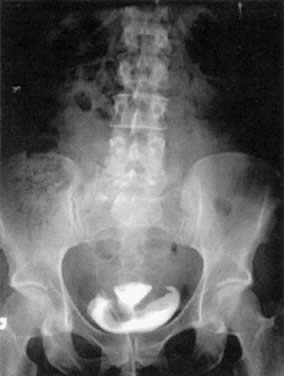

The combination of cystometry and radiographic techniques has made it possible to study the pressure changes in the lower urinary tract while monitoring its appearance with fluoroscopy or ultrasound. This type of study is called videocystourethrography. Although some find that fluoroscopy adds little to the evaluation,123 many find it useful. It is rarely used, however, because of its expense and the need for dedicated space to house the fluoroscopic and urodynamic equipment. Anatomic assessment and documentation with corresponding functional analysis of urethral, detrusor, and abdominal pressures clearly make this an optimal system to analyze urinary tract pathology. The alternative is to evaluate the anatomic changes with endoscopy, pelvic examination, and Q-tip testing (described previously) separate from the multichannel urodynamic assessment and to integrate the information mentally. The major disadvantages of videocystourethrography are the radiation exposure (1 rad), cost, and need for radiology personnel and space. Fluoroscopic evaluation of the bladder may help to clarify whether low-pressure, involuntary detrusor contractions are symptomatic or whether a patient's bladder neck funnels with increases in intra-abdominal pressure. Bladder neck funneling at rest may define an incompetent bladder neck in the patient with intrinsic sphincteric deficiency or type III incontinence that should be treated with periurethral injections of glutaraldehyde cross-linked (GAX)-collagen, autologous fat or carbon-coated beads.

Cystograms can be useful in cases of suspected fistulae (see Fig. 10) and bladder tumors. Figure 10 depicts a hysterosalpingogram in a woman with a vesicouterine fistula. Cystograms also can be used to evaluate bladder neoplasms, but cystoscopy is preferable.

Fig. 10. A hysterosalpingogram demonstrating a vesicouterine fistula after a vaginal birth. This patient previously had a cesarean section.